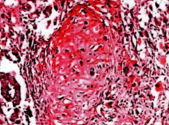

(单选题)病变镜下观如图所示,特征性病变为( )

A:心肌间质中血管扩张充血

B:纤维结缔组织增生

C:心肌细胞萎缩

D:风湿小体形成

E:淋巴细胞浸润

(单选题)箭头所指为何种细胞( )

A:淋巴细胞

B:纤维母细胞

C:巨噬细胞

D:异物巨细胞

E:Aschoff细胞